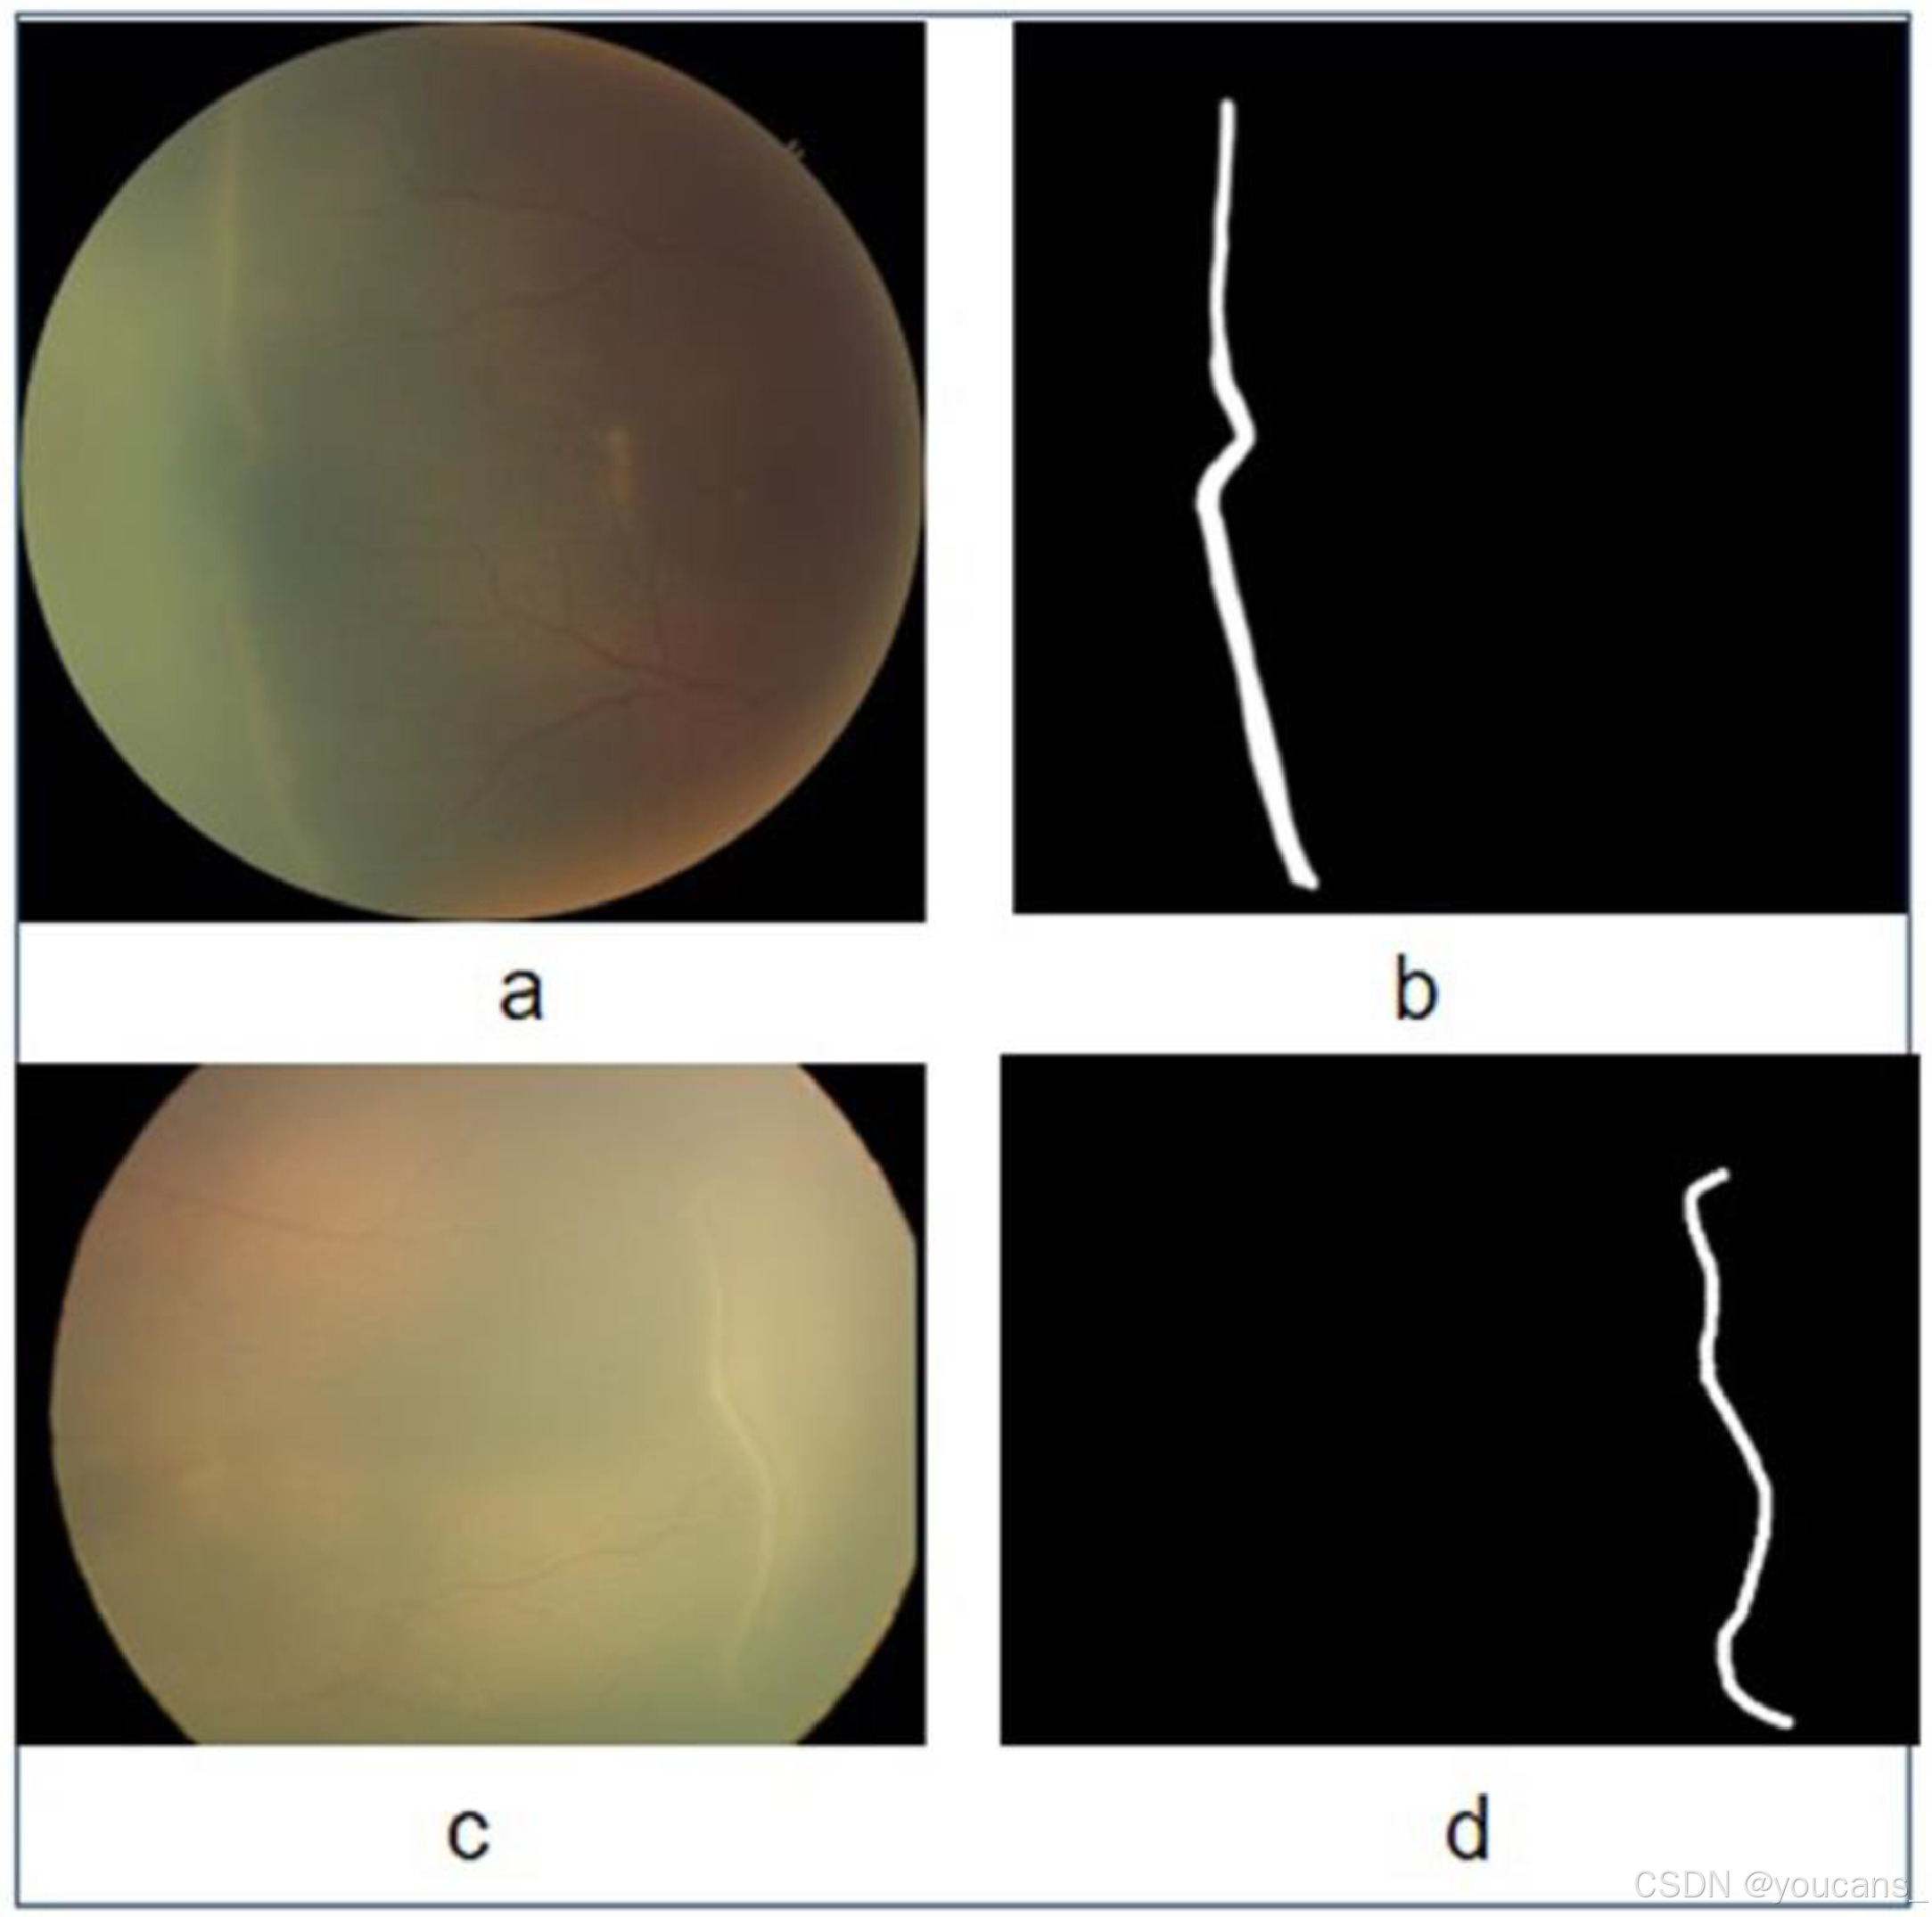

3.5 分界线/脊线分割图像

HVDROPDB-RIDGE 数据集 专门用于 分界线/脊线(Demarcation Line/Ridge) 的分割。

该数据集包含了 100张来自 后部视图(posterior view) 和 颞视图(temporal view)的图像,其中包含了 ROP 1期、2期和3期 的不同阶段。如图 6 所示,每张图像都有对应的分割掩膜图像(Ground Truth)。

HVDROPDB-BV 数据集包含4 个子集,每个子数据集各有50幅图像。

- RetCam_Ridge_images:通过 RetCam 成像系统 捕获的分界线图像。

- RetCam_Ridge_masks:与 RetCam 对应的分界线掩模图像。

- Neo_Ridge_images:通过 Neo 成像系统 捕获的分界线图像。

- Neo_Ridge_masks:与 Neo 对应的分界线掩模图像。

图6:用于分界线/脊线分割的原始图像和掩模:(a)Neo 原始图像,(b)Neo 掩模图像,(c)RetCam 原始图像,(d)RetCam 掩模图像。